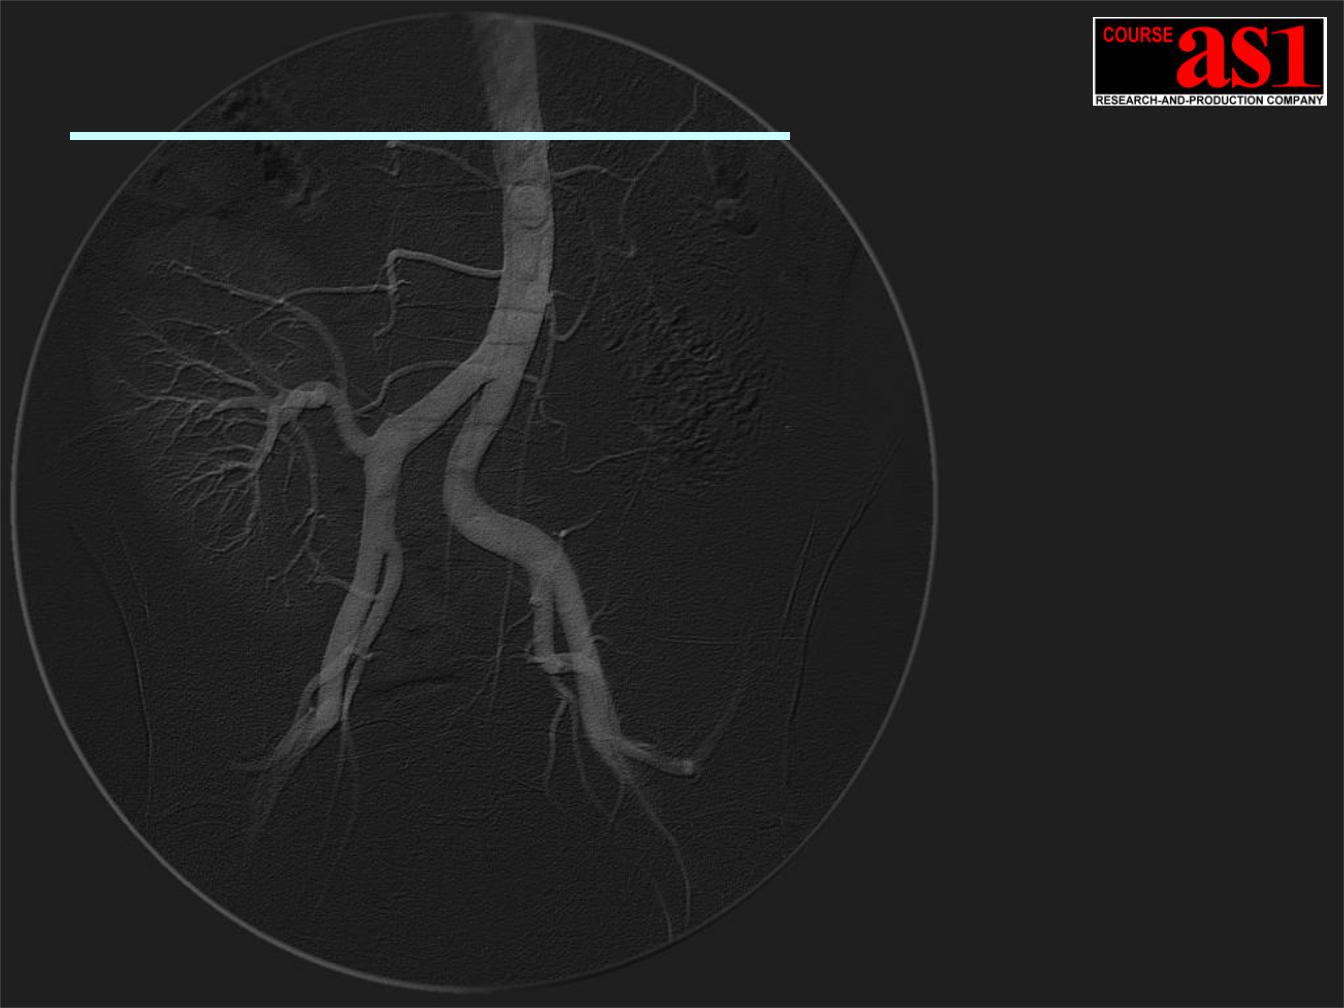

Проект – “100 микрон”

Ангиографическая Система Сверх Высокого Разрешения с Потоковой 2D Обработкой и Визуализацией Реального Времени (1080 MB/s)

с интегрированным Компьютерным X-Ray Томографом Сверхвысокого Разрешения.

-10.5(12.0) / 2.1(3.0) Мегапикселей при 60/120 кадр/сек.

-Формат поля 300(400)x300 mm / 100 mkm пиксель /

Снижение рентгеновской дозы в 20 раз!! Аналогов не существует !!